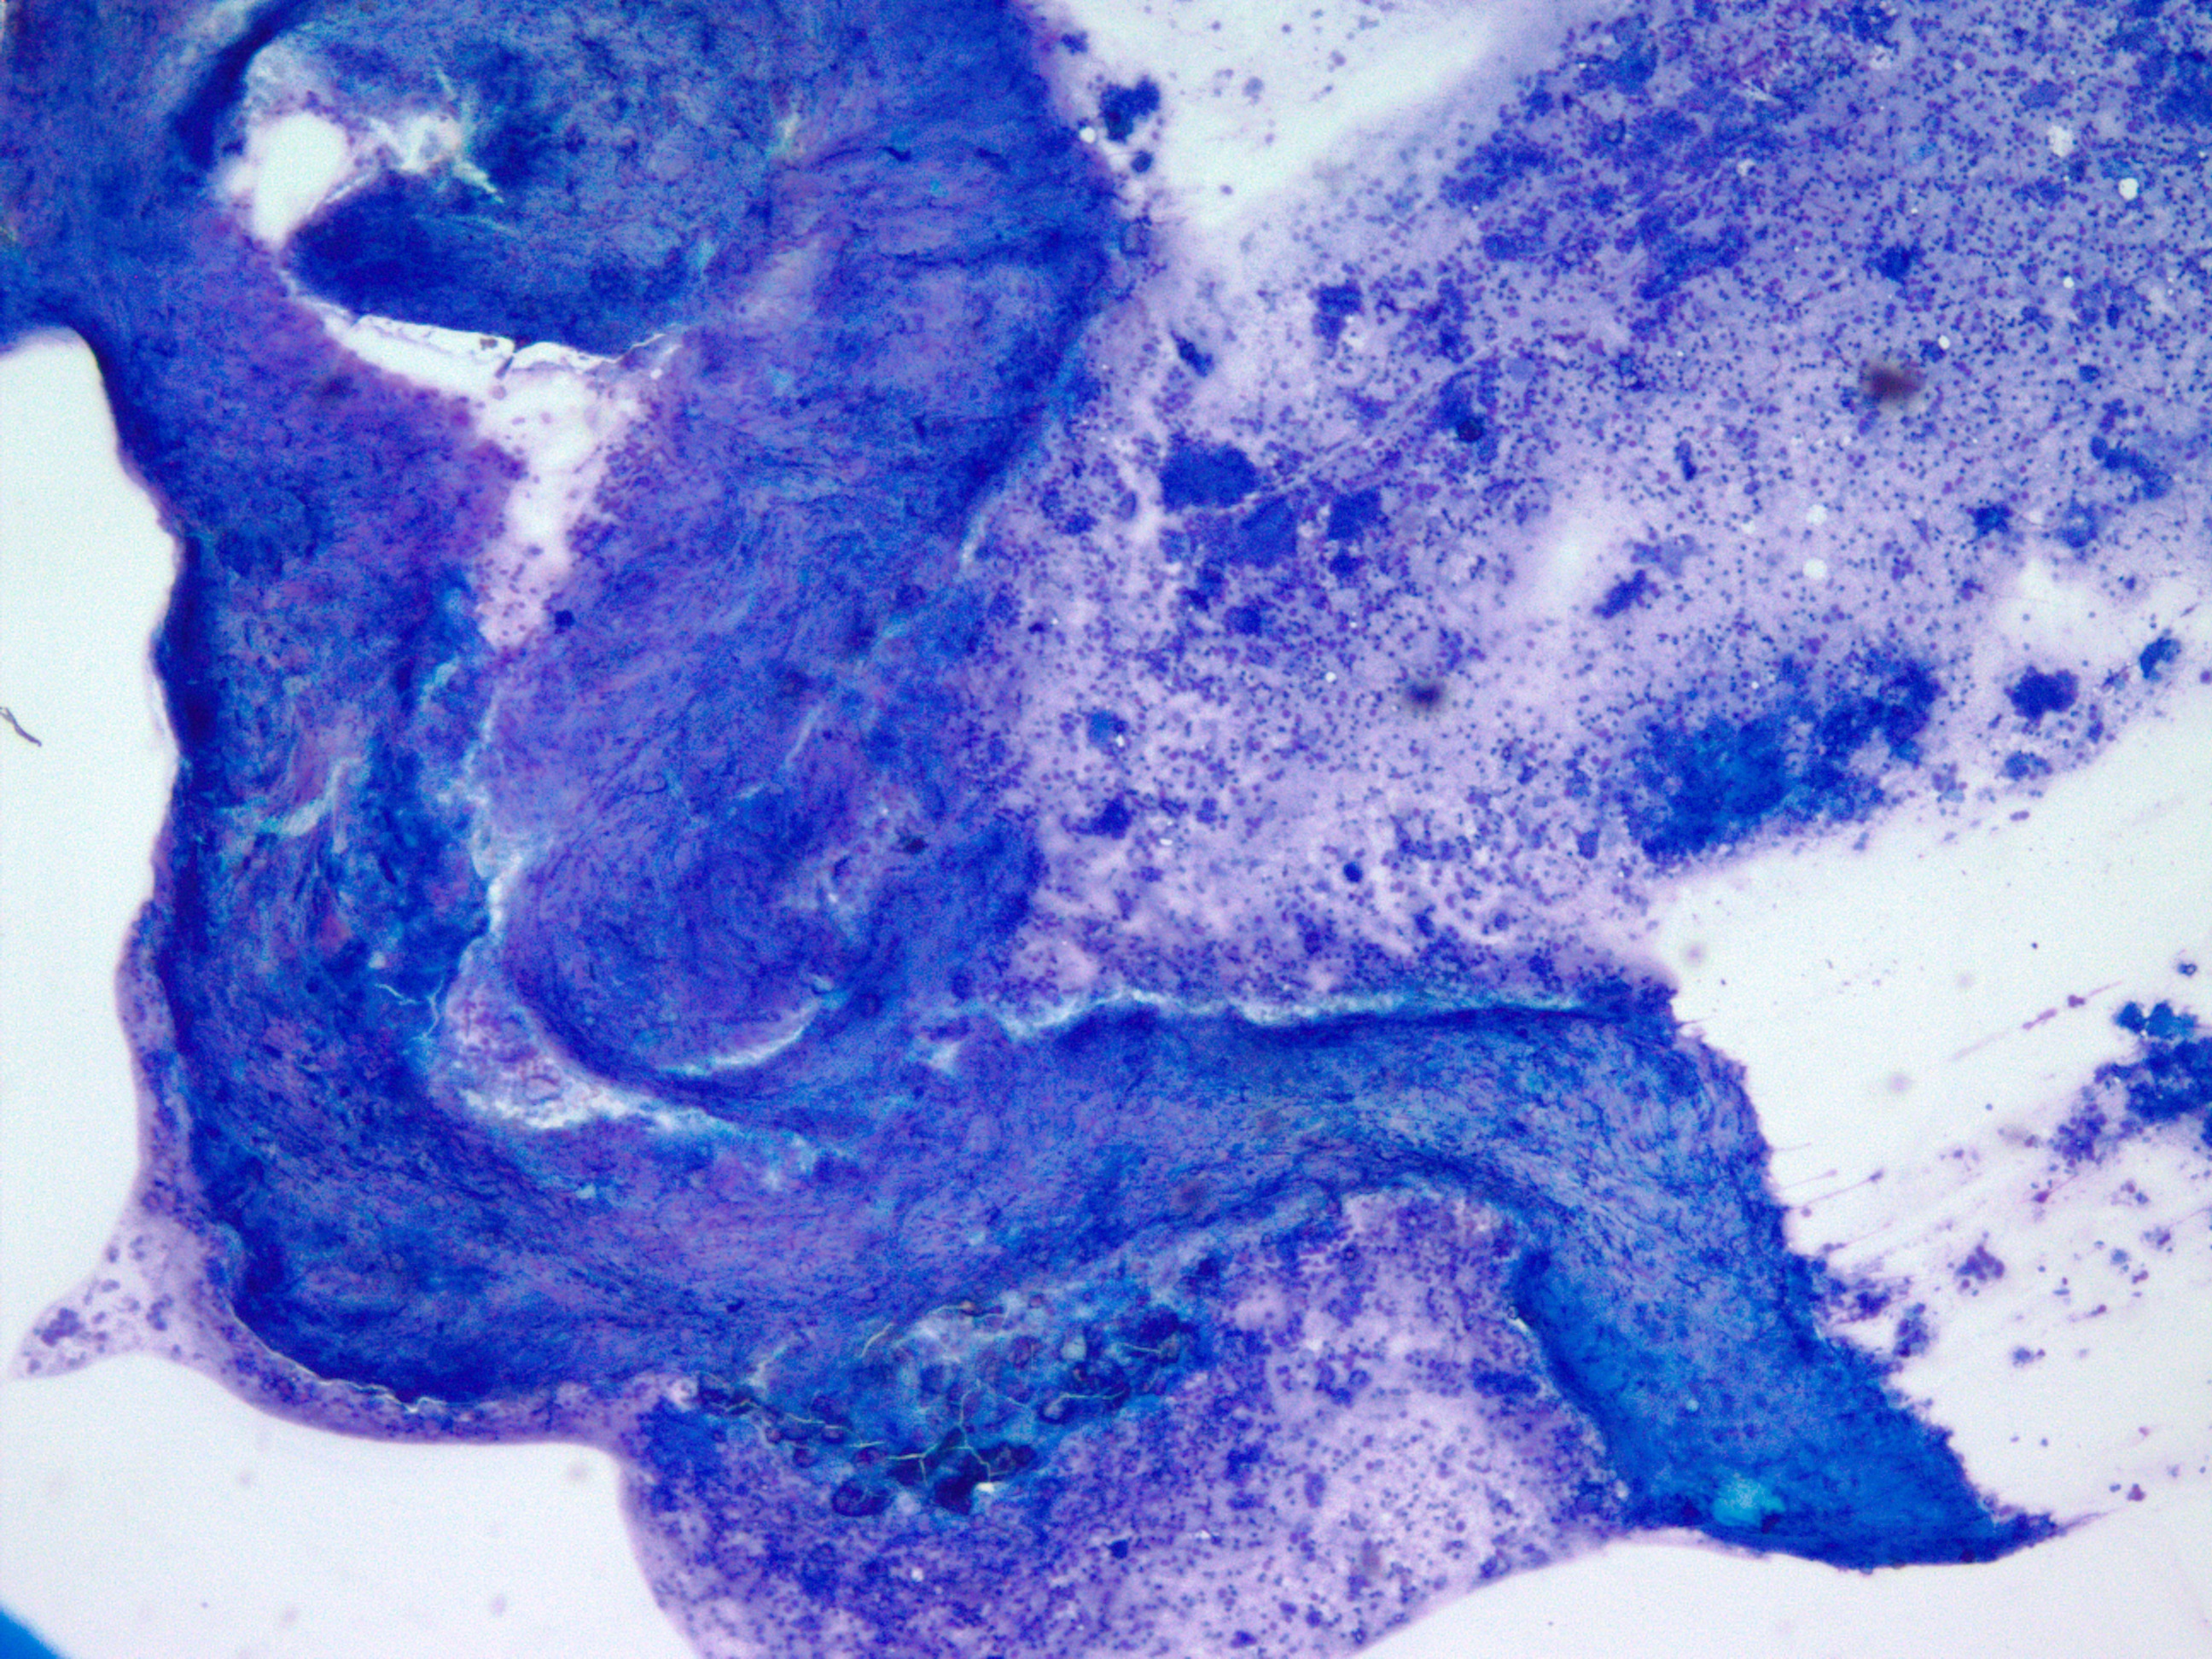

Specimen Type: FNA Station 4L, 4R Lymph Nodes, Modified Romanowsky smears, Papanicolaou smears, Thin Prep® Non-Gyn slide, H&E Cellient® Cell Block

Cytology:

When reviewing the slides cytologically, there is moderate to high cellularity, with malignant cells present in three-dimensional cohesive groups as well as scattered single cells.1,7 Compared to the background population, these cells appear enlarged and demonstrate increased nuclear-to-cytoplasmic ratios, irregular nuclear borders and contours, and prominent nucleoli with variable chromatin patterns.1 Nuclear pleomorphism is present, and occasional multinucleated tumor cells can be identified.1 The cytoplasm is moderate in amount and appears vacuolated due to mucin production, which reflects glandular differentiation with extracellular mucin and necrotic debris present in the background.1,2 Overall, these cytologic findings are characteristic of an epithelial glandular cell malignancy. Because adenocarcinoma shares overlapping cytologic features with other poorly differentiated tumors, IHC stains such as TTF-1 and Napsin A are used to help confirm pulmonary origin.1,7